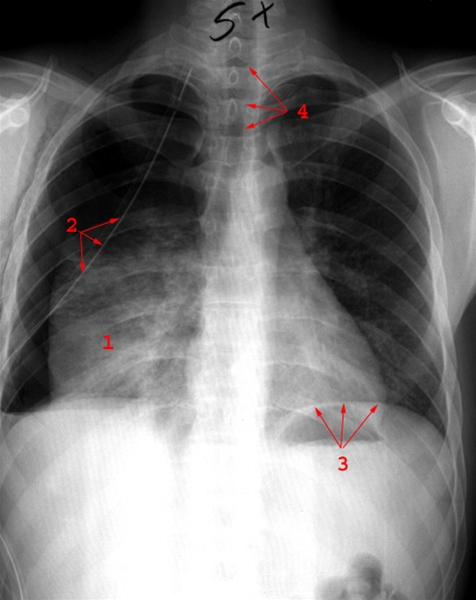

Røntgenbilledet viser højresidig pneumothorax med pleuradræn

1. Sammenklappet lunge

2. Pleuradræn

3. Venstre diafragmakuppel og luft i mavesækken

4. Trachea